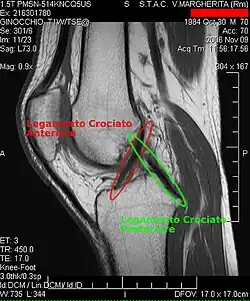

Die Diagnose kann mit bildgebenden Verfahren – namentlich der Magnetresonanztomographie (MRT, „Kernspin“) – bestätigt werden. Dabei ist allerdings zu beachten, dass die Interpretation der MRT in der Diagnostik eines Kreuzbandrisses zu 20 Prozent falsche Diagnosen liefert. Hier kommt es auf die sogenannten Schnittbilder und die geeignete Positionierung des Kniegelenkes bei der MRT-Untersuchung an. Der Radiologe sollte die genaue Vorgeschichte kennen, die zur Verletzung führte, und auch Erfahrung in der Untersuchung eines verletzten Gelenkes haben, um Fehlbeurteilungen zu vermeiden. Im Vergleich zur MRT liegt die Fehlerquote bei dem erheblich einfacher durchzuführenden Lachman-Test bei nur 10 Prozent.[85][86][87][88] Die MRT ist daher in der Regel zur Diagnose eines vorderen Kreuzbandrisses weniger sensitiv und weniger spezifisch als die klinische Befundung durch einen qualifizierten Orthopäden.[89] Das Ergebnis einer MRT hat nur relativ selten einen Einfluss auf die klinische Entscheidungsfindung[90] und sollte keinen Ersatz für eine sorgfältige Anamnese und Palpation darstellen.[15] Mehrere Studien kommen zu dem Schluss, dass eine MRT nur bei komplizierteren unklaren Knieverletzungen – und dabei eher zum Erstellen einer Ausschlussdiagnose[91] – sinnvoll ist.[92][93]

Röntgenaufnahmen leisten keinen unmittelbaren Beitrag zur Diagnosestellung einer Kreuzbandruptur. Beide Kreuzbänder sind – ob gerissen oder nicht – im Röntgenbild nicht sichtbar. Wird dennoch geröntgt, so kann dies der Diagnosestellung von möglichen knöchernen Begleitverletzungen dienen.